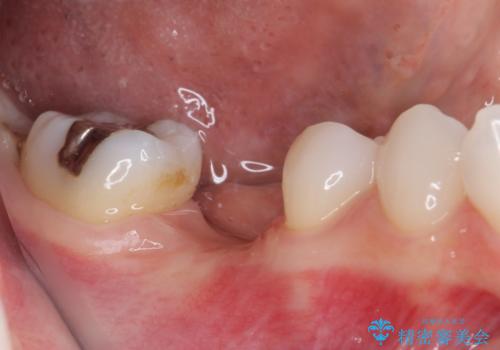

機能性と清掃性、更には審美性も考慮し、土台となるアバットメントにはジルコニアカスタムアバットメントを採用しました。

ジルコニアカスタムアバットメントは、歯肉ラインに金属が見えにくいというだけでなく、クラウンを装着する土台の形が天然歯と近い形態となるため、清掃性が高く歯肉が腫れにくいというメリットがあります。